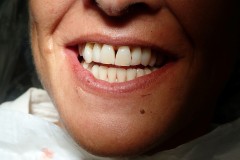

This young patient was self-conscious about the appearance of her short teeth and gummy smile. Through crown lengthening and tooth whitening procedures, we were able to create a beautiful, more mature smile.